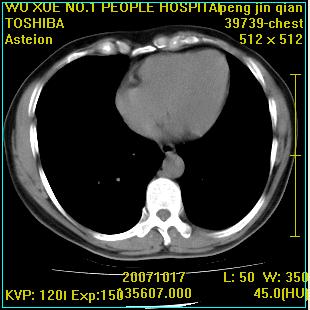

标题: CT10148:男,56岁,咳血。 [打印本页]

标题: CT10148:男,56岁,咳血。

左肺上叶尖后段较大团块影,边缘光滑,内见不规则裂隙样空洞,周围明显见细小结节及渗出,与肺门方向结构紊乱,另:左上叶尖段外侧 舌叶内侧 右上叶尖段及下叶背段均见片状致密影。考虑:继发性肺结核伴空洞形成!

左肺上叶尖后段较大团块影,边缘光滑,内见不规则裂隙样空洞,周围明显见细小结节及渗出,与肺门方向结构紊乱,另:左上叶尖段外侧 舌叶内侧 右上叶尖段及下叶背段均见片状致密影。考虑:继发性肺结核伴空洞形成!建议进一步检查,除外肺癌

右肺下叶背段/左上肺/左下肺结核伴空洞形成

结核 空洞伴两肺播散